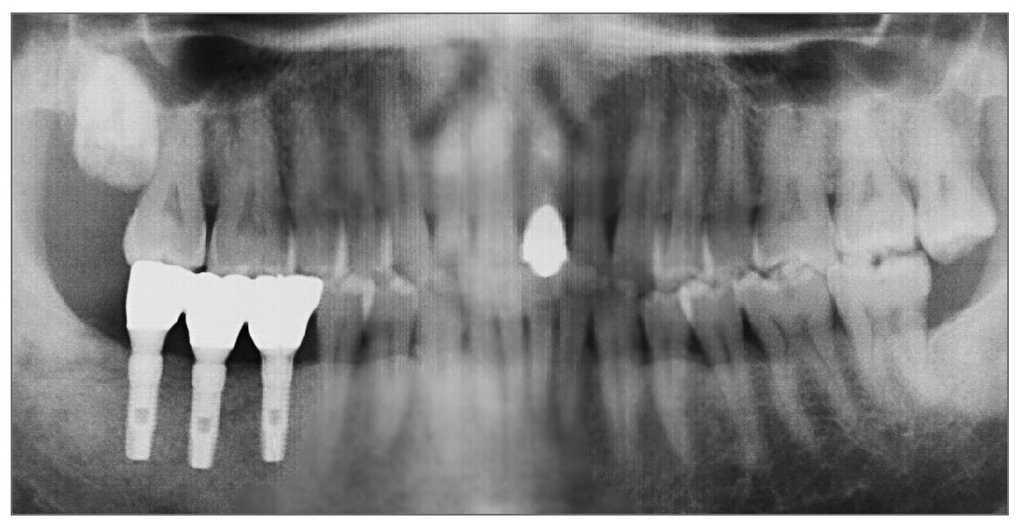

Figura 8 (derecha). Radiografía panorámica tomada en la evaluación final.

El área curó sin incidencias y pocas molestias. La imagen oclusal a los tres meses de la cirugía mostraba una buena cicatrización sin exposición de la membrana ni del implante (fig. 13). La segunda cirugía se llevó a cabo 3 meses después de la colocación del implante, y se consiguió una cobertura media del defecto del 52% (rango 40% a 63%) (fig. 14). La prótesis continuó funcionando correctamente hasta la evaluación final (figs. 15 y 16).

Figura 16 (derecha). Radiografía periapical en la evaluación final.